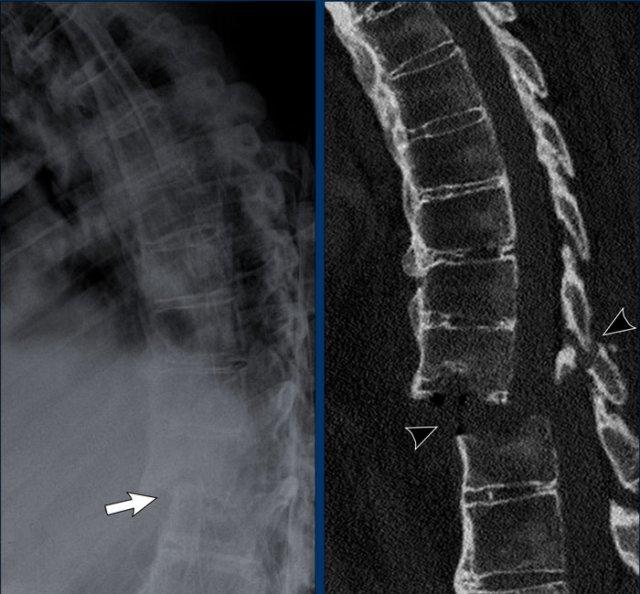

Gai xương Syndesmophyte

Các hình ảnh này cho thấy gai xương syndesmophyte ở cột sống thắt lưng và vôi hóa dây chằng cạnh sống.

Khi các gai xương syndesmophyte này hợp nhất lại, chúng tạo ra hình ảnh “cột sống tre” điển hình.

Cũng cần lưu ý hiện tượng vôi hóa đĩa đệm gian đốt sống và dính khớp liên mấu.

Gai xương syndesmophyte có hướng thẳng đứng đặc trưng.

Hiện tượng bắc cầu và hợp nhất khá phổ biến.

Hậu quả là cột sống mất tính linh hoạt và có thể dễ dàng gãy ngay cả sau một chấn thương nhỏ.

Cột sống tre

Hình ảnh cột sống tre trong viêm cột sống dính khớp.

Hợp nhất cột sống thắt lưng do gai xương syndesmophyte và vôi hóa dây chằng cạnh sống.

Lưu ý vôi hóa dây chằng (mũi tên).

Cột sống tre cứng đờ dễ bị gãy do cơ chế ưỡn quá mức, ngay cả sau chấn thương nhẹ.

Luôn cần nghi ngờ cao về các gãy xương này ở bệnh nhân có cột sống cứng!

Cột sống tre thường bắt đầu ở đoạn thắt lưng và có thể lan lên đến cột sống cổ.

Lưu ý hình vuông hóa thân đốt sống (mũi tên).

Tình trạng dính khớp do DISH và viêm cột sống dính khớp có thể dẫn đến cột sống cứng đờ. Khi đó, cột sống dễ bị gãy ngay cả sau chấn thương nhẹ. Các gãy xương này thường là gãy do cơ chế ưỡn quá mức (hyperextension).

Bệnh nhân này bị chấn thương nhẹ, nhưng đã dẫn đến gãy xương ưỡn quá mức không vững với các biến chứng thần kinh.

Điểm cần ghi nhớ: cần luôn có chỉ số nghi ngờ cao đối với gãy xương do ưỡn quá mức ở bệnh nhân có cột sống cứng đờ do DISH và viêm cột sống dính khớp.